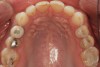

(3.) Preoperative occlusal view of lower arch with orthotic in place.

Figure 3

(4.) Preoperative occlusal view of upper arch.

Figure 4

Ultimately, the patient developed joint and muscle symptoms due to his lack of posterior support and sought the help of a specialist. His bite was analyzed, and he was fitted with a dental orthotic that allowed his teeth to touch in centric relation (Figure 3). This was intended to be a temporary measure to stabilize the patient's bite and make him comfortable, but before any permanent treatment could be carried out, he moved abroad and had been living with the device for more than four years before the time of the consultation. He stated that his bite was now very stable with the orthotic, but he was looking for a more permanent solution and also wanted to improve the overall appearance of his smile.

A comprehensive examination was carried out, and preoperative photographs were taken (Figure 1 through Figure 4). The patient presented with fair oral hygiene and slight, generalized tissue inflammation. Caries and defective restorations were detected on teeth Nos. 4, 5, 13, and 14. The crown on tooth No. 12 was showing signs of leakage, and although the endodontic access cavity had been temporarily restored with composite, this endodontic re-treatment was acceptable and the tooth was otherwise symptom-free. Erosion was present on most of the posterior teeth and the cuspids, and abrasion was noted on teeth Nos. 4, 5, 10, 11, 20, 21, 22, 28, and 29. An examination of the patient's muscles, joints, and bite revealed no joint sounds, a normal range of motion, and negative joint load and immobilization tests.

The patient's removable dental orthotic covered the lower bicuspids and first molars. With the orthotic in place, there was shim stock contact on all posterior teeth and on the second molars that were not covered by the appliance. However, there was no incisal overlap and a lack of anterior guidance.11 When the orthotic was removed, solid shim stock contacts were present on the second molars and the right lateral incisor. These contacts were reproduced every time the appliance was removed. The same contacts were found on the patient's mounted models, which confirmed that the joints were in centric relation. Whether the lower second molars had overerupted as a result of wearing the appliance or had already been in this position before the orthotic was fitted could not be established. Apart from these three contacts, no other teeth touched, and there was a 2-mm space between the posterior teeth, making mastication difficult. Interestingly, wear facets were present on the palatal surfaces of the upper central and lateral incisors, indicating that at some point in time, there had been significant overlap of the anterior teeth and a possible constriction of the chewing envelope. Analysis of a cephalometric radiograph showed a class II growth tendency with a reduced mandibular plane angle, which supported the theory that the patient had at one time possessed a class II occlusion.